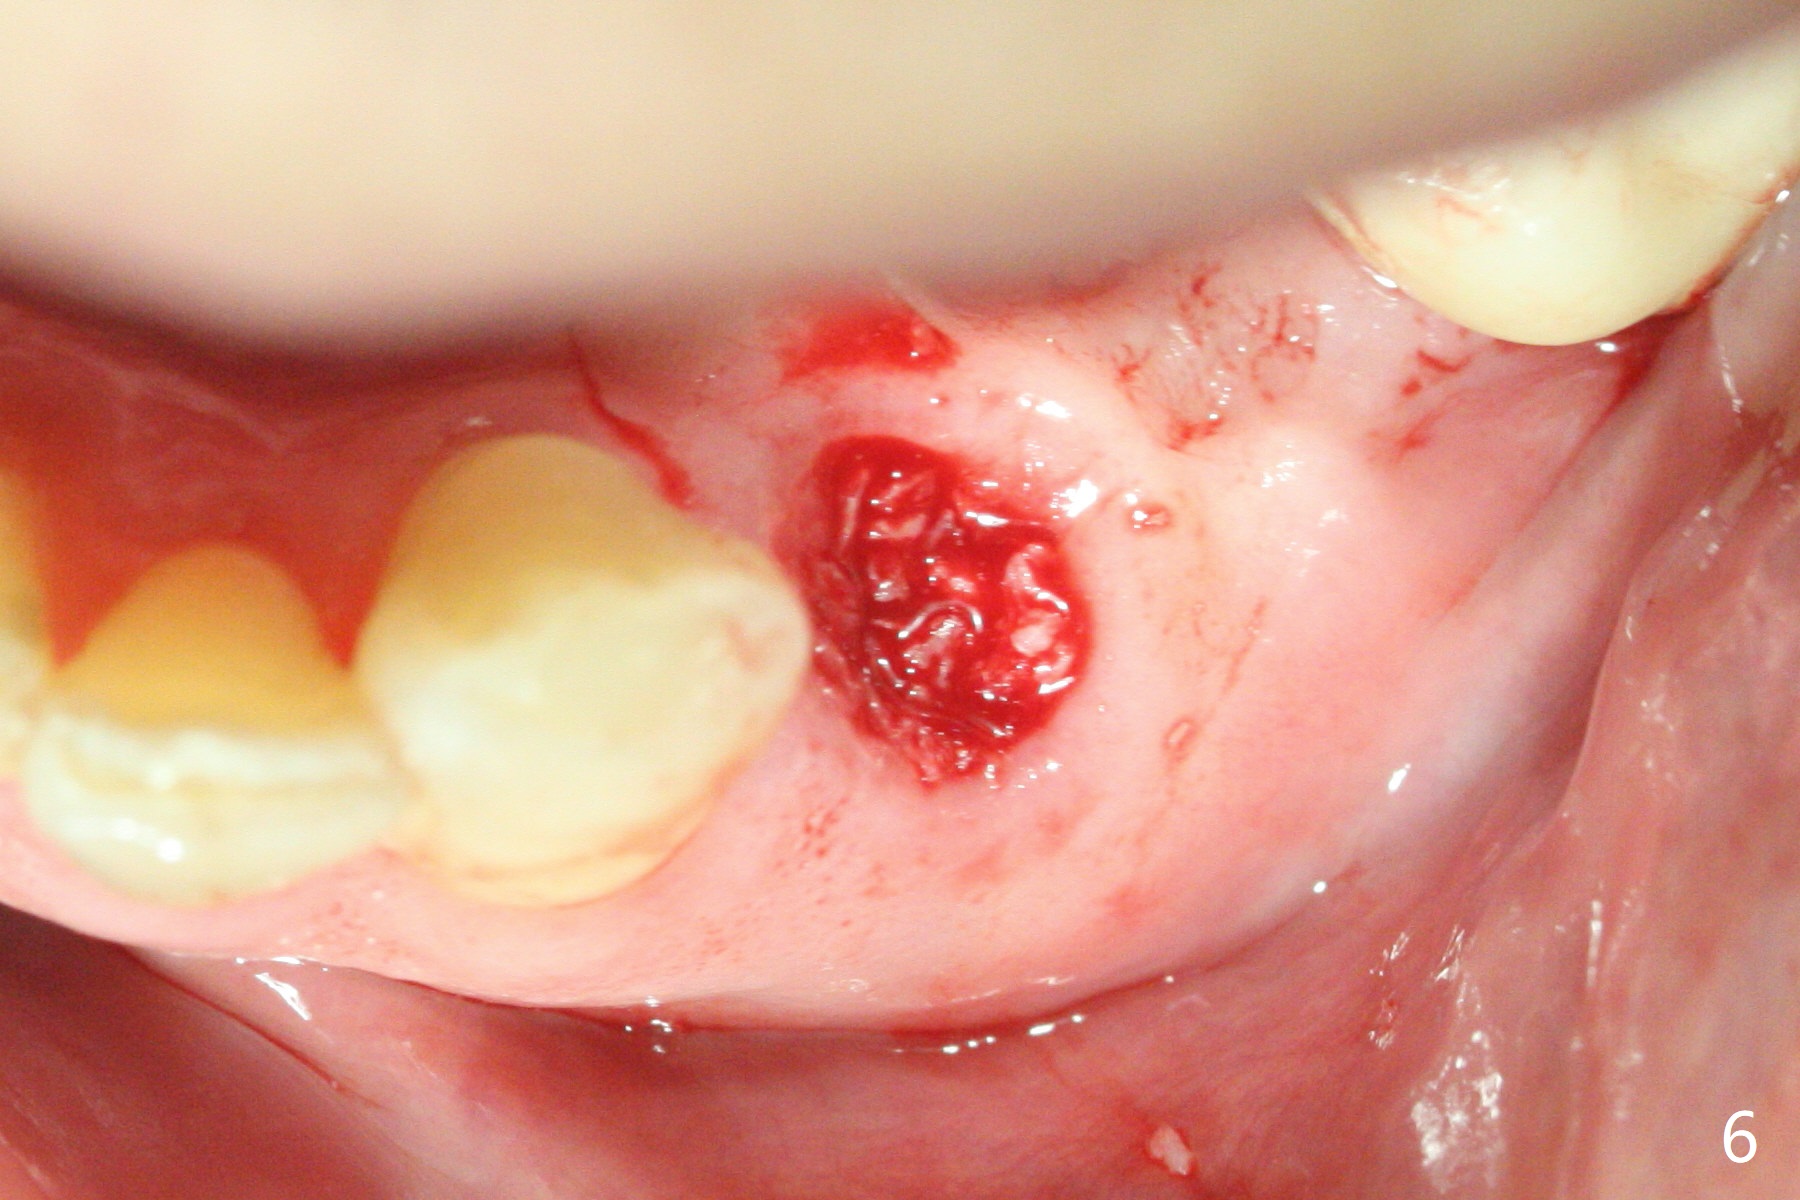

A 73-year-old man with history of stroke presented to office with #20 chewing pain 2 years ago (Fig.1). When he returns today, the tooth #20 has lost, while #21 has mobility (Fig.2), torus mandibularis (Fig.3 *) and severe bone loss, as related to Class V defect (Fig.4). As expected, the buccal plate is lost, the buccal gingiva blanching and bulging due to a curette underneath (Fig.5 *). After placement of allograft in the socket (Fig.6,8 *), a 8x8 mm BioXclude and 4-0 PGA suture are used to close the socket (Fig.7). Periodontal dressing stays in place 10 days postop (Fig.9). The patient is pleased with hemostasis. He is going to return his home state.